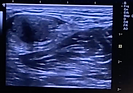

Ultrasound-guided technique to optimize suture placement